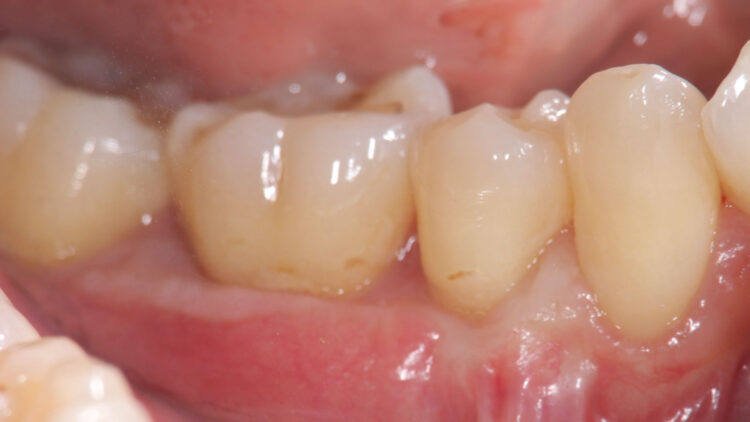

- 【術後】奥歯の歯肉退縮症例②